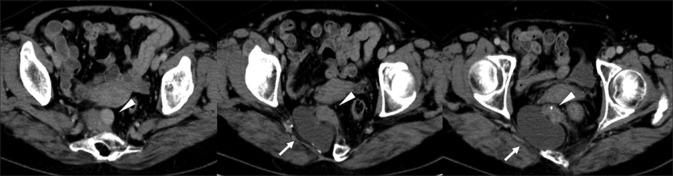

We present a case of a 59-year-old woman with a malignant tumor arising within presacral teratoma associated with Currarino syndrome (CS). A characteristic crescent-shaped sacrum was detected on preoperative image examination and the presacral mass was pathologically diagnosed as a malignant tumor associated with CS. To our knowledge, this is the first case report of presacral teratoma associated with CS coexisting with both adenocarcinoma and a neuroendocrine tumor.

我们报告一例59岁女性,其骶前畸胎瘤内出现恶性肿瘤,伴有库拉里诺综合征(CS)。术前影像检查发现特征性的新月形骶骨,骶前肿块经病理诊断为与CS相关的恶性肿瘤。据我们所知,这是首例与CS相关的骶前畸胎瘤同时合并腺癌和神经内分泌肿瘤的病例报告。